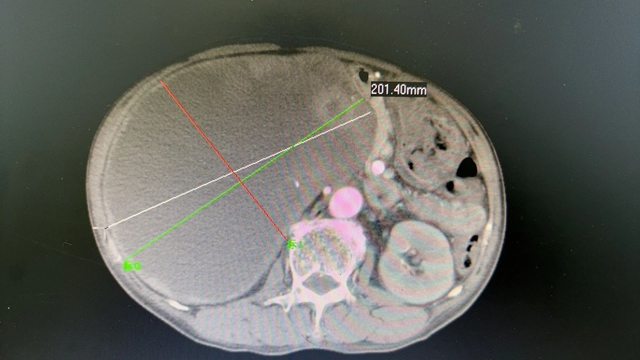

近日,合江县中医医院泌尿外科·男科团队在多学科协助下,成功为一右肾巨大肿瘤患者实施了根治性切除术,肿瘤直径达20厘米。

患者男性,75岁,因腹痛难忍到医院就诊,在体检时发现右肾巨大肿瘤伴消化道出血(肿瘤波及肠道关系),重度贫血,低蛋白血症,双下肢重度水肿,在泌尿外科·男科住院治疗。

科室副主任周伟联合多学科(输血科、消化内科、呼吸内科、肿瘤科、普外科、肛肠科、麻醉科)参与救治,待患者平稳后,由周伟主刀,顺利为患者开展了腹腔镜下右侧巨大肾癌根治性切除术,手术顺利。